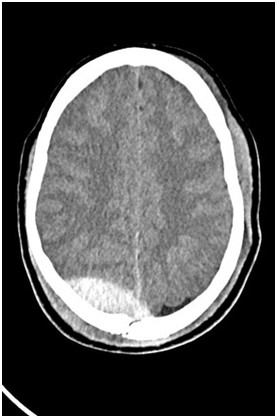

Na załączonym obrazie przedstawiono obraz TK głowy u pacjenta po urazie. Wskaż fałszywe stwierdzenie dotyczące przedstawionej patologii.